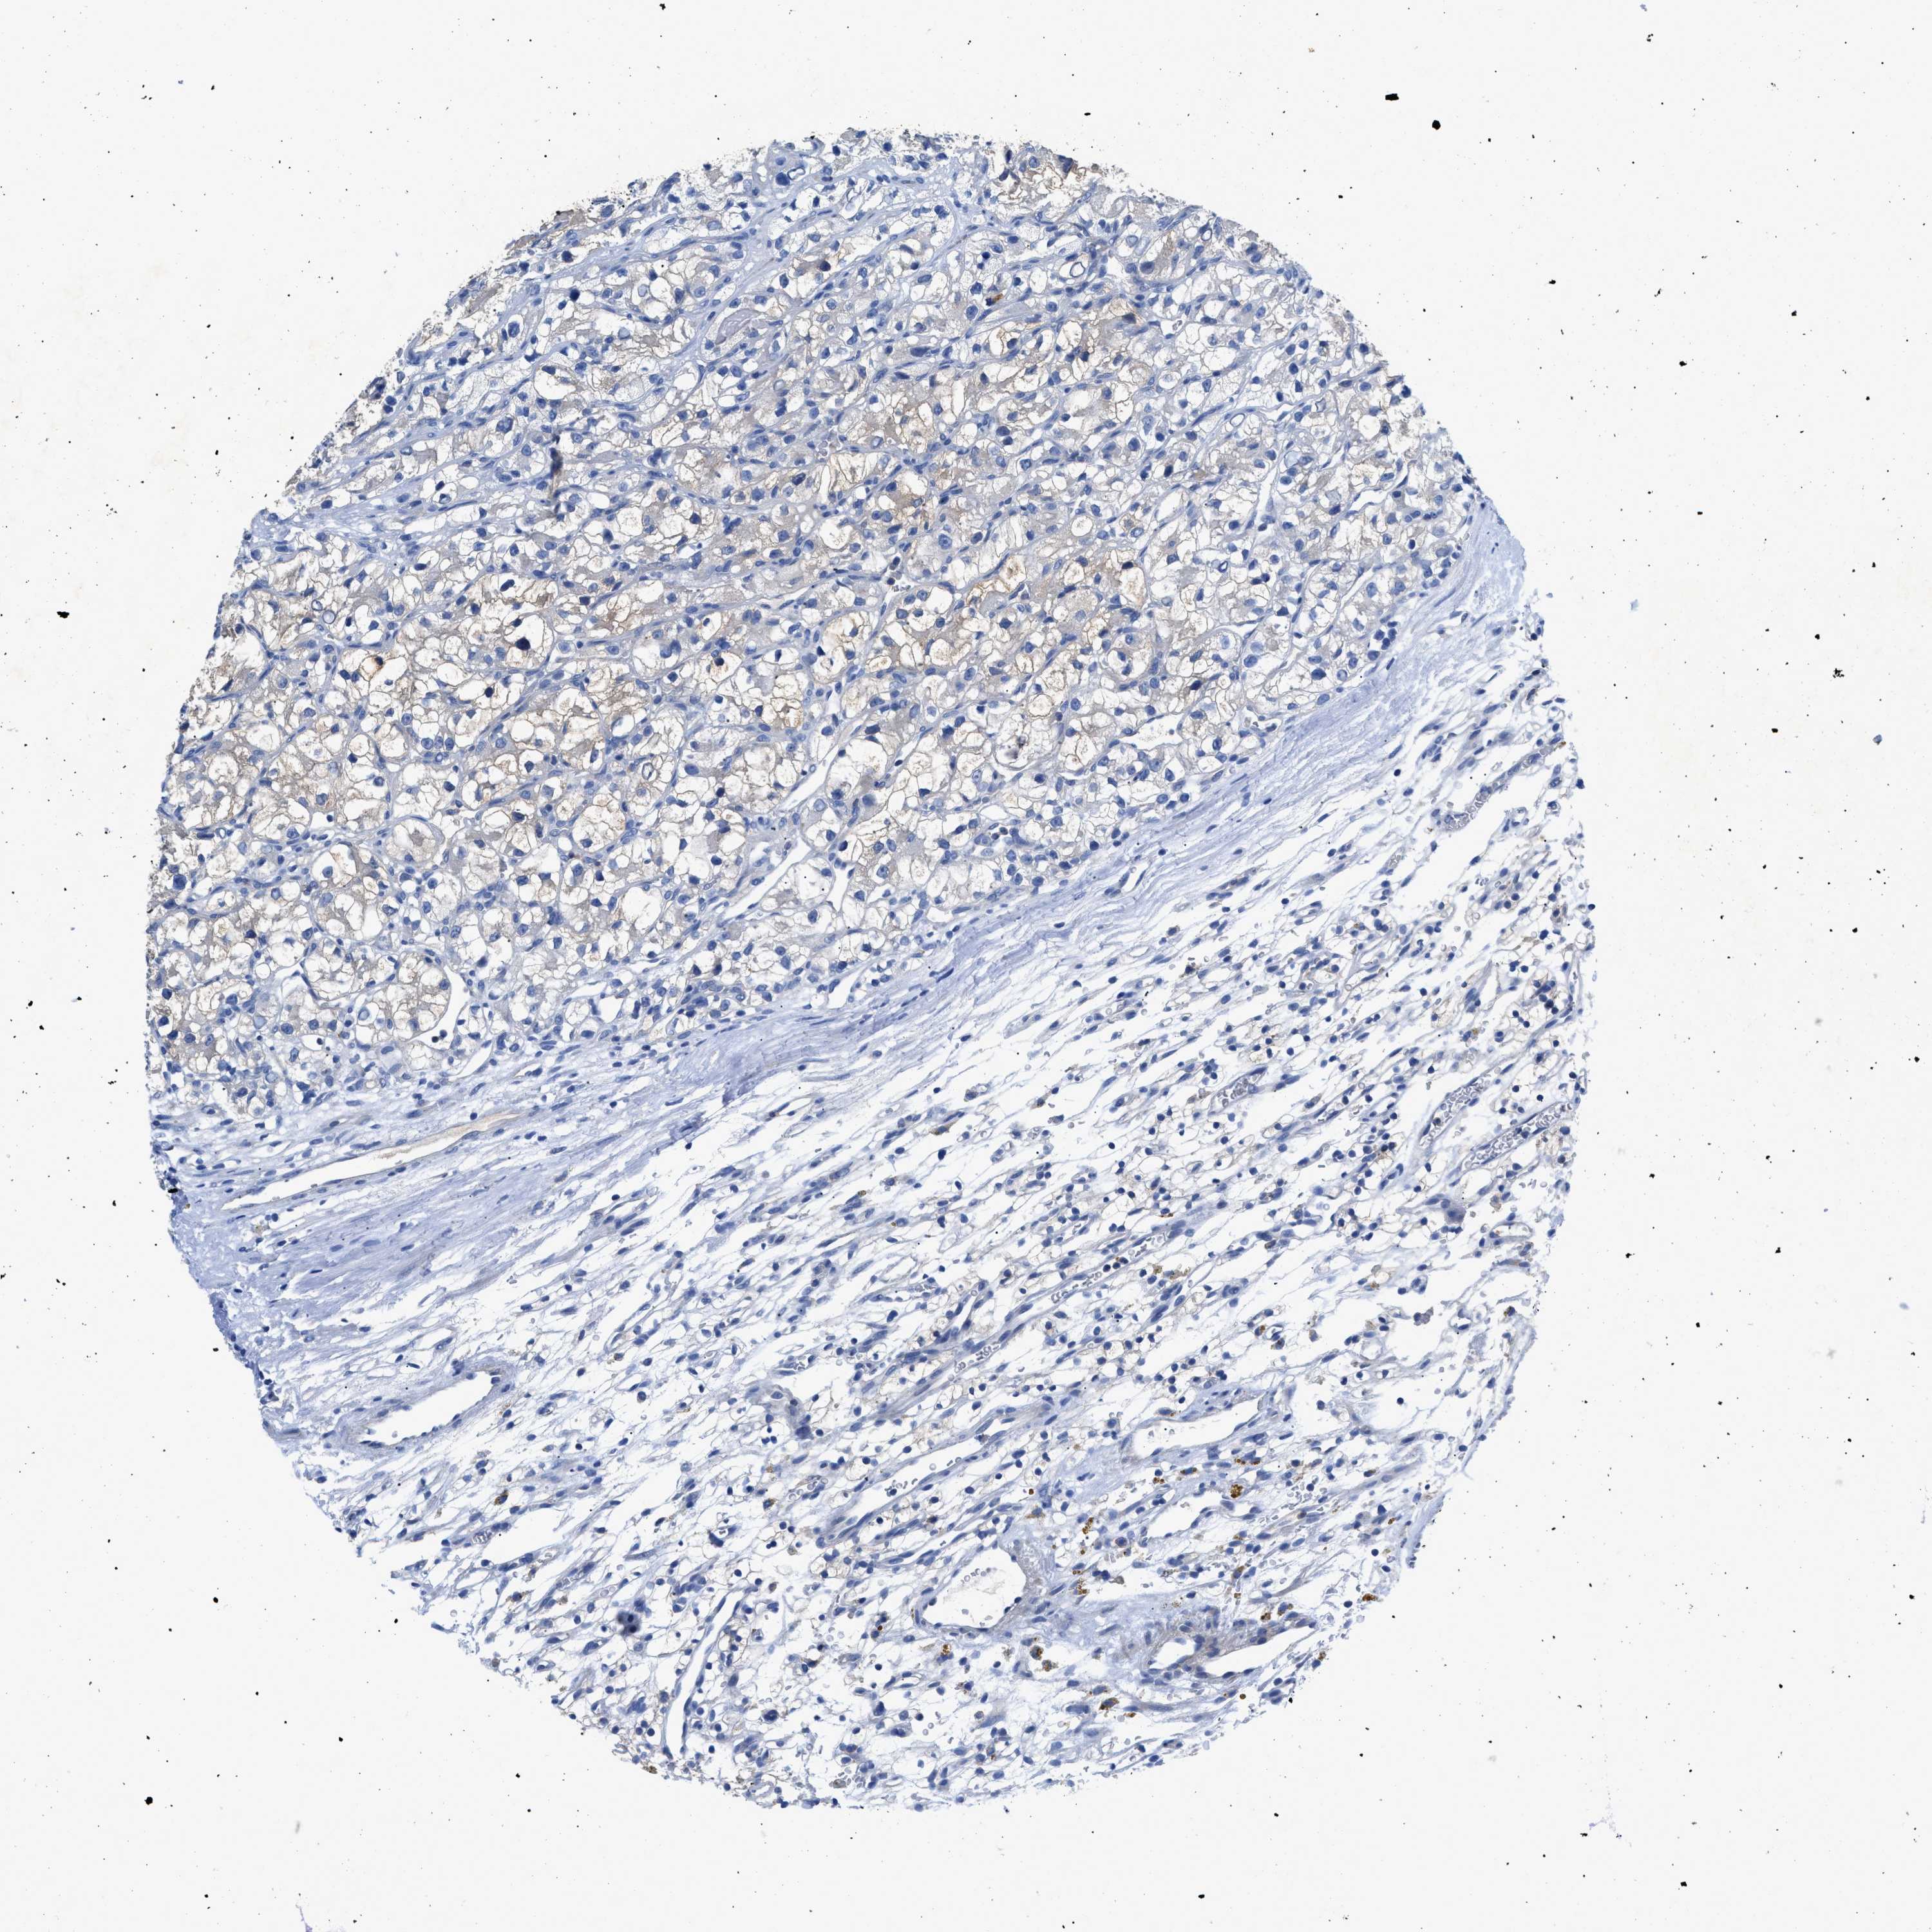

KIDNEY RENAL CLEAR CELL CARCINOMA (VALIDATION) - Interactive survival scatter ploti

The Survival Scatter plot shows the clinical status (i.e. dead or alive) for all individuals in the patient cohort, based on the same data that underlies the corresponding Kaplan-Meier plots. Patients that are alive at last time for follow-up are shown in blue and patients who have died during the study are shown in red.

The x-axis shows the expression levels (FPKM) of the investigated gene in the tumor tissue at the time of diagnosis. The y-axis shows the follow-up time after diagnosis (years). Both axes are complimented with kernel density curves demonstrating the data density over the axes. The top density plot shows the expression levels (FPKM) distribution among dead (red) and alive patients (blue). The right density plot shows the data density of the survived years of dead patients with high and low expression levels respectively, stratified using the cutoff indicated by the vertical dashed line through the Survival Scatter plot. This cutoff is automatically defined based on the FPKM cutoff that minimizes the p-score. The cutoff can be changed by dragging the vertical line or by entering a cutoff value in the square labeled "Current cut-off".

Under the Survival Scatter plot the p-score landscape (black curve; left axis) is shown together with dead median separation (red curve; right axis). Dead median separation is the difference in median mRNA expression between patients who have died with high and low expression, respectively. It is calculated as follows: median FPKM expression of dead patients with high expression - median FPKM expression of dead patients with low expression. This is intended to aid the user in visually exploring custom cutoffs and the associated p-scores and dead median separation.

Individual patient data is displayed and can be filtered by clicking on one or more of the category buttons on the top of the page. Categories describing expression level and patient information include: high, low, alive, dead, female, male and tumor stages. The scale of the x-axis can be toggled between linear and log-scale by clicking on the "x log" button. Mouse-over function shows TCGA ID, patient information and mRNA expression (FPKM) for each patient.

& Survival analysisi

Kaplan-Meier plots summarize results from analysis of correlation between mRNA expression level and patient survival. Patients were divided based on level of expression into one of the two groups "low" (under cut off) or "high" (over cut off). X-axis shows time for survival (years) and y-axis shows the probability of survival, where 1.0 corresponds to 100 percent.

SLC10A6 is validated prognostic, high expression is favorable in Kidney Renal Clear Cell Carcinoma (validation)

Best expression cut offi

Based on the FPKM value of each gene, patients were classified into two groups and association between prognosis (survival) and gene expression (FPKM) was examined. The best expression cut-off refers the FPKM value that yields maximal difference with regard to survival between the two groups at the lowest log-rank P-value. Best expression cut-off was selected based on survival analysis .

When clicking on this number, the vertical dashed line indicating cut-off, the interactive survival plot, and the Kaplan-Meier curve will be adjusted to show results based on the best expression cut-off.

: 1.34

Average pTPM 1.6

Number of samples 100